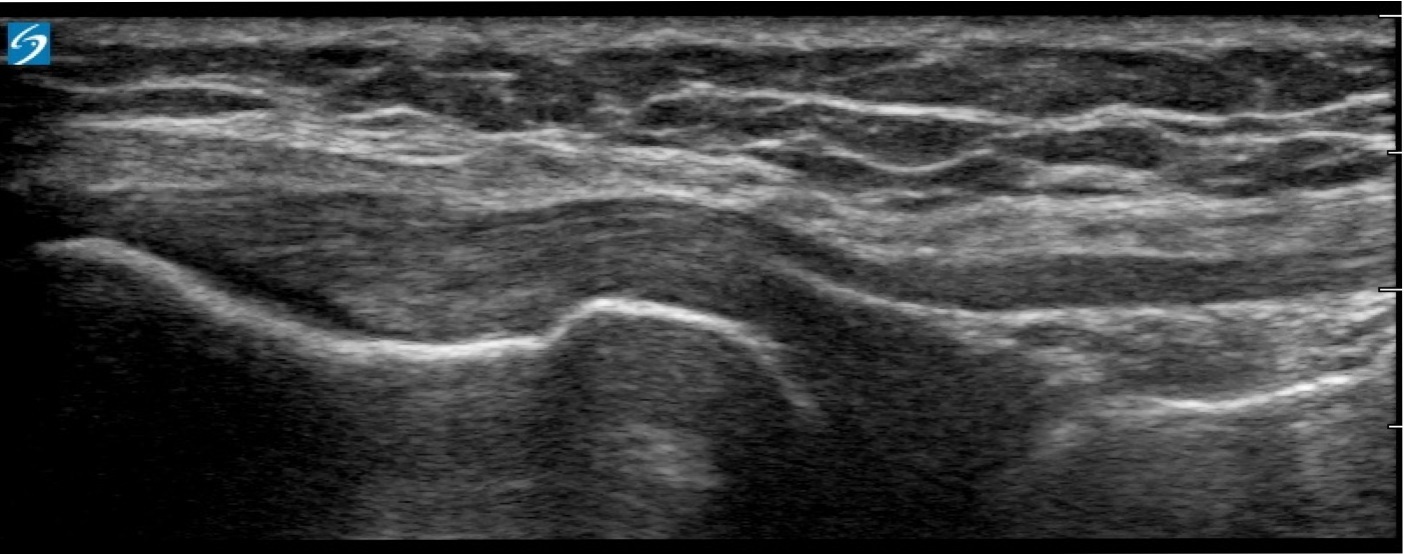

Knee Lateral Proximal LCL Image